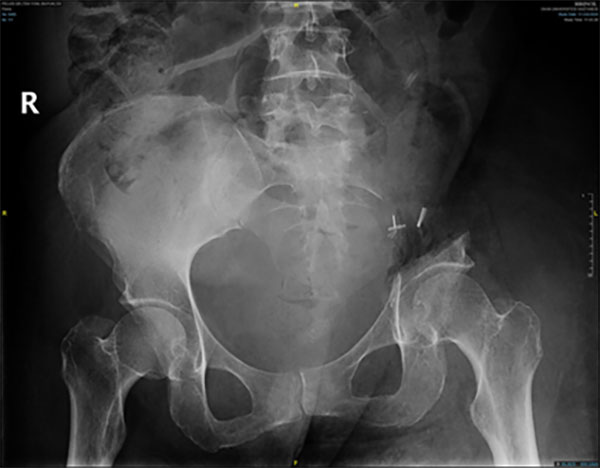

Ameliyat Sonrası: Röntgende sol sakroiliak rezeksiyon görülmekte.

Röntgende sol sakroiliak rezeksiyon görülmekte.